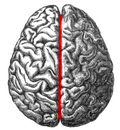

Brain: Lateral view

- Longitudinal fissure - divides cerebrum into hemispheres.

- Lateral sulcus (Sylvian fissure, lateral fissure) - separates temporal lobe from frontal lobe & parietal lobe.

- Central sulcus - separate parietal lobe from frontal lobe.